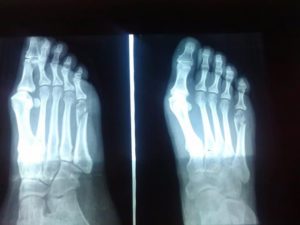

- Выполняет инструментальное обследование. Для постановки точного диагноза необходимо проведение рентгена в трех проекциях. Если есть подозрение на внутрисуставный или многооскольчатый перелом, то проводится магнитно-резонансная или компьютерная томография.

Однако, с целью постановки точного диагноза и определения разновидности перелома, пациентам назначается обязательное рентгенографическое исследование, позволяющее выявить все возможные сколы и смещения. Рентгеновский снимок делается в трех проекциях.

При любом переломе, а особенно 5-й плюсневой кости, осуществляется рентгенография стопы в 3-х проекциях: боковая, переднезадняя и косая.